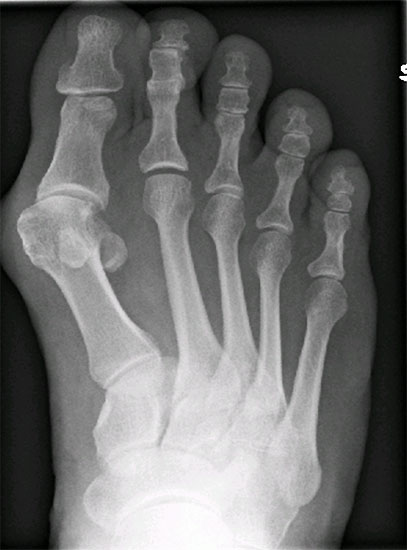

Im Falle einer Insuffizienz des 1. Strahles wird in jedem Falle eine TMT-I-Arthrodese indiziert sein, hier dient der Intermetatarsalwinkel planerischen Aspekten im Sinne des Ausmaßes der Korrektur am Os cuneiforme I. Die Bestimmung des Metatarsus adductus-Winkels dient der Detektion eines Pes adductus. Im Falle des Vorliegens einer solchen Deformität sind ggf. auch Korrekturosteotomien an den kleineren Metatarsalia zu erwägen, um ausreichend Platz für die Einstellung des Metatarsale I in die Rectusposition zu erhalten. Ein weiteres wichtiges Kriterium in der a.p.-Projektion stellt das Längenverhältnis von Metatarsale I zu Metatarsale II dar, da bei der Durchführung der TMT-I-Arthrodese das Vorliegen einer Minusvariante häufiger die Gefahr einer postoperativen Transfermetatarsalgie birgt und hier unter Umständen über Modifikationen des operativen Vorgehens nachgedacht werden sollte. Hier besteht die Möglichkeit von alternativen Präparationsverfahren im TMT I oder aber der Durchführung einer Interpositionsarthrodese des TMT I zur Verlängerung des 1. Strahles. Alternativ können auch Verkürzungsosteotomien des 2. und 3. Strahles erwogen werden. Als indirekte radiologische Zeichen einer Insuffizienz des 1. Strahles kann ein Klaffen des Spaltes zwischen dem Os cuneiforme mediale und dem Os cuneiforme intermedium sowie eine Hypertrophie der Corticalaes des Metatarsale II gedeutet werden (Abb. 6).